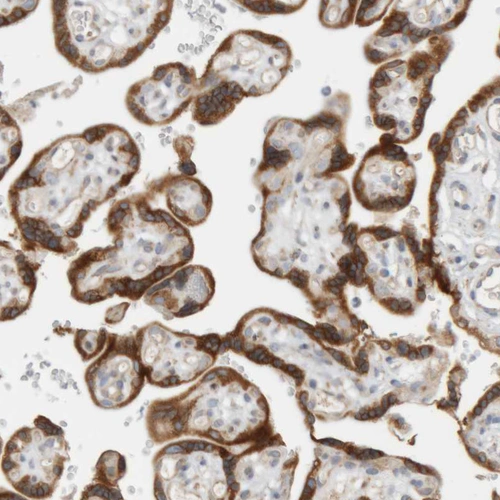

Immunohistochemistry analysis in human epididymis and skeletal muscle tissues using HPA025922 antibody. Corresponding RPN2 RNA-seq data are presented for the same tissues.